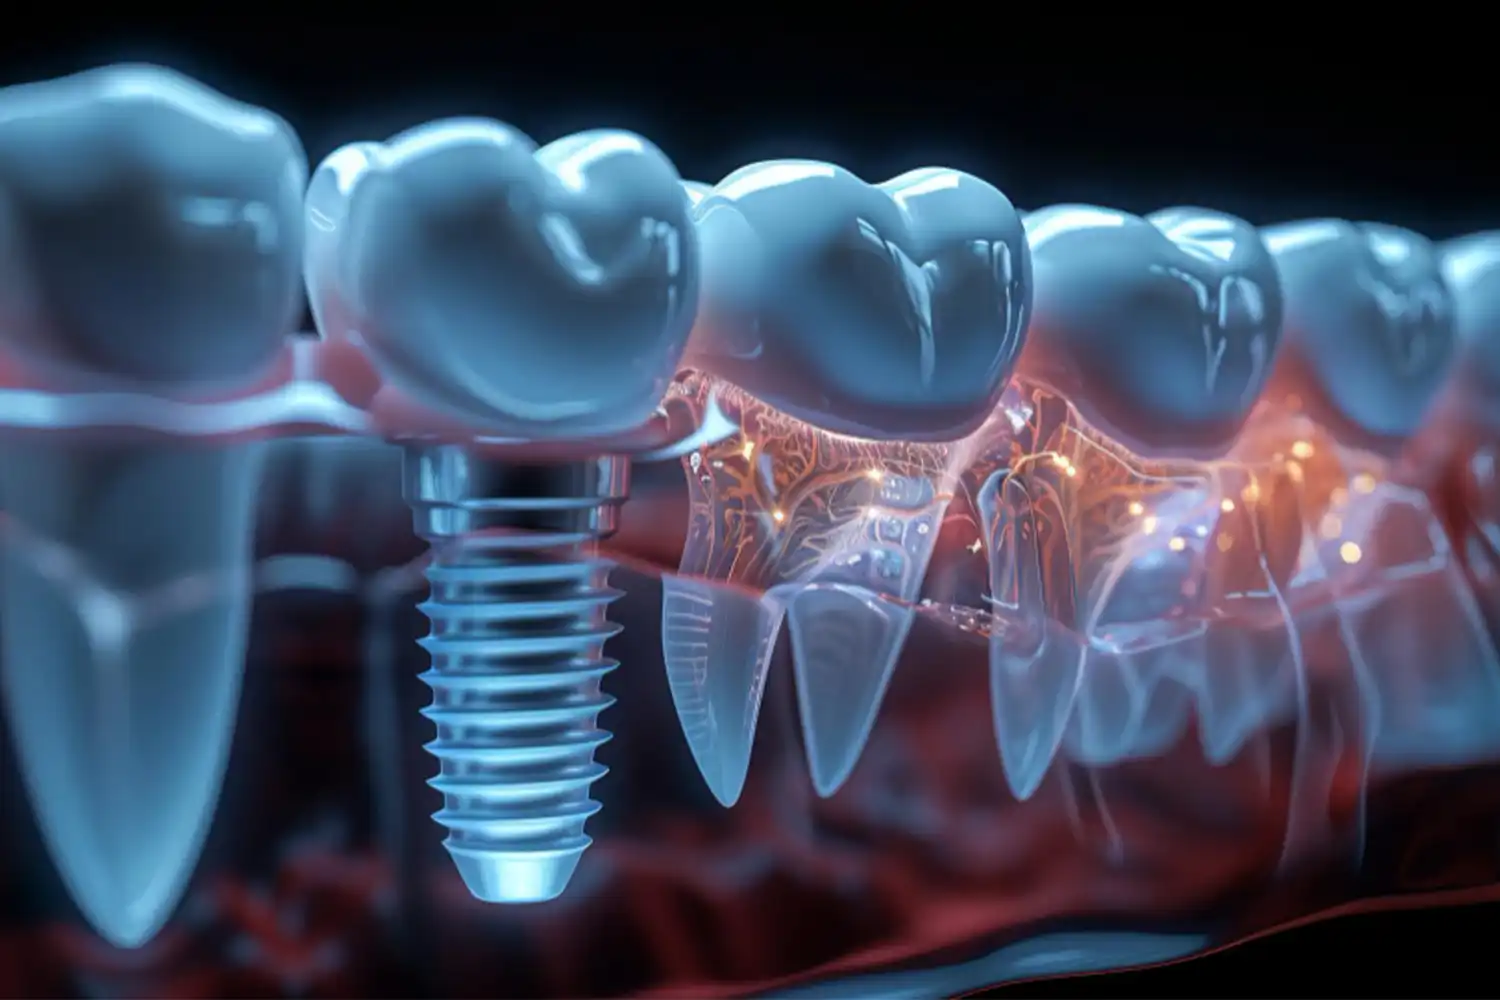

İmplant tedavisi, eksik dişlerin yerini doğal bir şekilde doldurmak için çene kemiğine yerleştirilen titanyum köklerin üzerine protez dişlerin sabitlenmesiyle yapılan bir tedavi yöntemidir. Bu yöntem, hem estetik hem de fonksiyonel açıdan doğal dişlere en yakın sonuçları sunar. Aşağıda implant tedavisi hakkında daha detaylı bilgi bulabilirsiniz:

İmplant tedavisi, çene kemiğine yerleştirilen biyouyumlu bir titanyum vida sayesinde eksik dişin doğal işlevini ve görünümünü geri kazandırır.

İmplant, diş kökü görevini görerek üzerine yerleştirilen protez dişi destekler.

Bu yöntem, hem tek diş eksikliklerinde hem de tam dişsizlik durumlarında uygulanabilir.

Titanyum Vida (İmplant Gövdesi): Çene kemiğine yerleştirilir ve zamanla kemikle kaynaşır.

Abutment (Bağlantı Parçası): İmplant gövdesi ile protez dişi birbirine bağlayan ara parça.

Protez Diş: Estetik ve fonksiyonel amaçla implant üzerine yerleştirilen diş formundaki yapı.